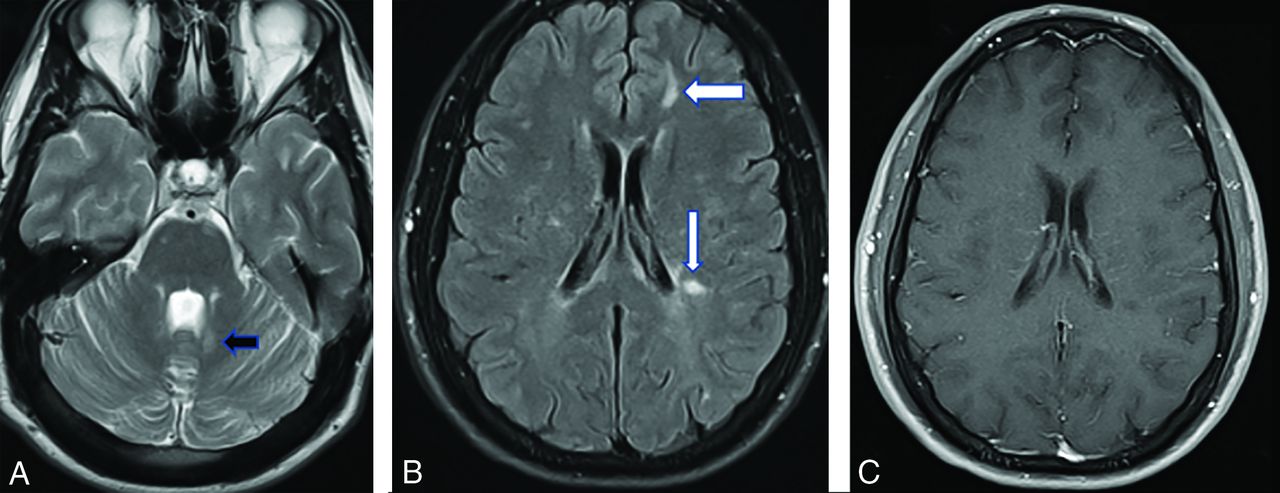

In other words, instead of using the Barkhof criteria as proposed in Okuda et al,9 the revised 2017 McDonald and/or MAGNIMS criteria should be applied (On-line Table). On the basis of the new guidelines, DIS in RIS is based on the presence of T2/FLAIR hyperintense lesions in at least 2 of the following topographies: cortical or juxtacortical white matter, periventricular white matter, spinal cord, and the infratentorial (brain stem and/or cerebellum) compartment (Fig 1).

A, Axial T2-weighted image in a 21-year-old patient presenting to the emergency department with the worst headache of her life shows left periventricular posterior fossa lesions (arrow). B, The FLAIR scan demonstrates periventricular (Dawson fingers-like) and juxtacortical lesions (arrows). C, None of the lesions show gadolinium enhancement.